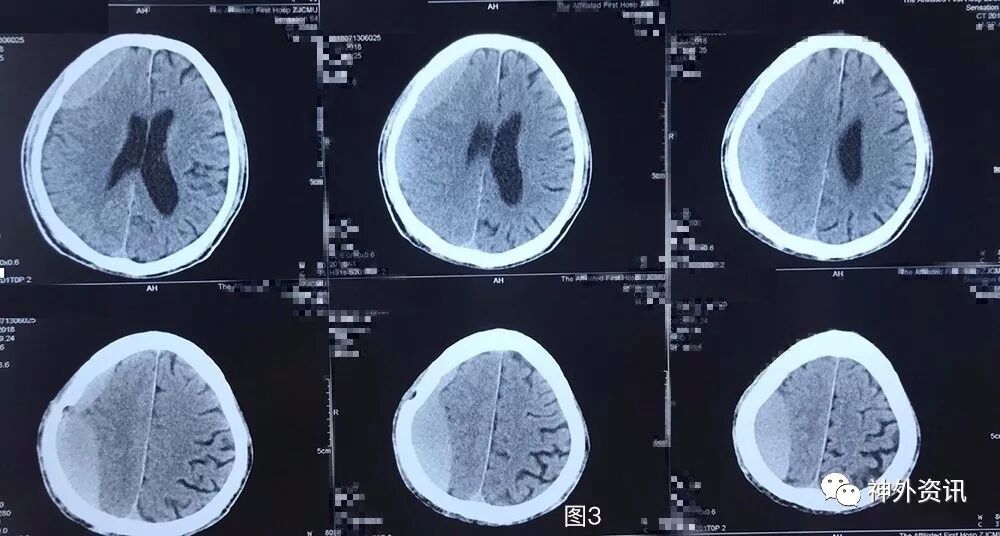

患者5月前不慎头部外伤,当时无黑懵晕厥,无头痛头晕,未重视治疗,3月余前无明显诱因下出现头痛,伴头晕,伴行走不稳,前往外院就诊,查头颅CT示:右侧额颞顶枕部慢性硬膜下血肿考虑(图1),行钻孔引流术。术后复查头颅CT提示右侧额颞顶枕慢性硬膜下血肿钻孔引流术后改变(图2),术后症状好转出院。2月前(术后1月)患者再次出现头痛晕头晕等症状,复查头颅CT:右侧额颞顶枕硬膜下血肿,脑实质受压,中线轻度左偏(图3)。遂再次行右额颞顶枕部硬膜下血肿钻孔引流术,术后患者头痛无明显好转,伴左侧肢体乏力,复查头颅CT见术后局部血肿形成(图4)并进行性增大(图5)。

图3. 外院第2次手术前头颅CT:右侧额颞顶枕硬膜下血肿复发,血肿为稍高密度,脑实质受压,中线轻度左偏。